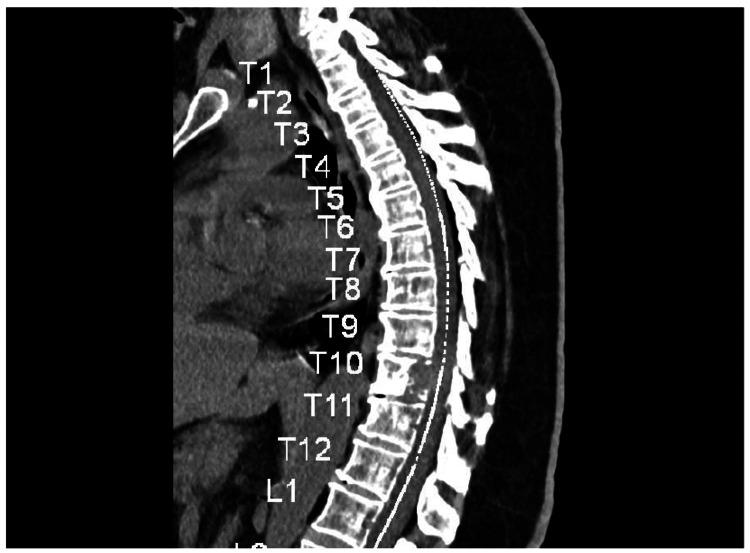

Papillary thyroid carcinoma (PTC) typically presents with an excellent prognosis. Distant metastasis, particularly to the spine, is rare and associated with poorer outcomes. This report highlights the importance of considering metastatic PTC in the differential diagnosis of persistent back pain in patients with thyroid abnormalities. A 61-year-old female presented with progressive lower back pain and an enlarging neck mass. Evaluation revealed a Thyroid Imaging Reporting and Data System, Category 4 (TIRADS-4) thyroid nodule and a lytic lesion in the T10 vertebra. Biopsy confirmed papillary thyroid carcinoma with metastasis to the spine. Spinal metastasis is an uncommon manifestation of PTC. This report underscores the need for vigilance regarding back pain in patients with a history of thyroid disease, as early detection can influence management and prevent complications. Spinal metastasis from PTC is rare but possible, even as a solitary lesion. Clinicians should consider PTC in the differential diagnosis of spinal lesions, particularly in patients with a history of thyroid abnormalities, to facilitate early diagnosis and treatment.

甲状腺乳头状癌(PTC)通常预后良好。远处转移,尤其是脊柱转移,较为罕见且与较差的预后相关。本报告强调了在甲状腺异常患者持续性背痛的鉴别诊断中考虑转移性PTC的重要性。一名61岁女性出现进行性下背部疼痛和颈部肿块增大。评估显示甲状腺影像报告和数据系统4类(TIRADS-4)甲状腺结节以及T10椎体溶骨性病变。活检证实为甲状腺乳头状癌伴脊柱转移。脊柱转移是PTC的一种不常见表现。本报告强调了对有甲状腺疾病史患者的背痛保持警惕的必要性,因为早期发现可影响治疗并预防并发症。PTC的脊柱转移虽罕见但有可能,即使是孤立性病变。临床医生在脊柱病变的鉴别诊断中应考虑PTC,尤其是有甲状腺异常病史的患者,以便于早期诊断和治疗。